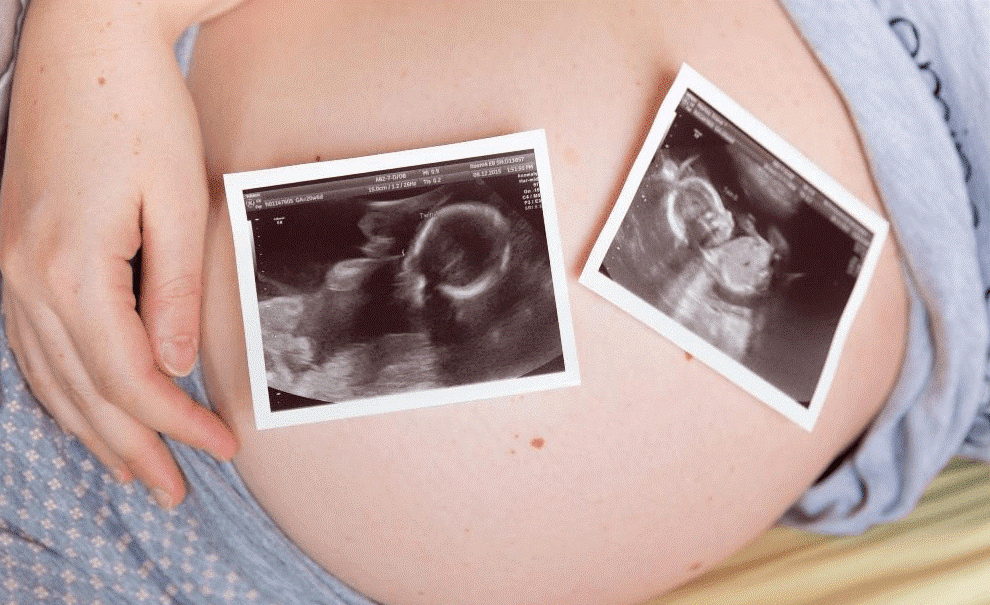

Фотографии и информация о многоплодной беременности на 12 неделях

Раздел: Фотоэссе